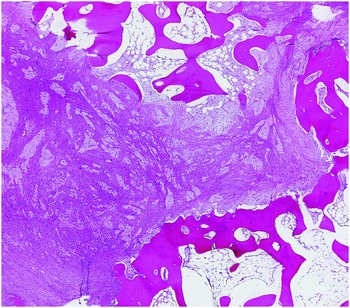

61g3pHBqBoL._AC_UF1000,, Diagnosis of bone and joint disorders : Resnick, Donald,

Diagnosis of bone and joint disorders : Resnick, Donald, Diagnosis of Bone and Joint Disorders: Resnick, Donald,

Diagnosis of Bone and Joint Disorders: Resnick, Donald, Diagnosis of Bone and Joint Disorders: Resnick, Donald,

Diagnosis of Bone and Joint Disorders: Resnick, Donald, 61sa2nN44qL.jpg,

61sa2nN44qL.jpg, fendo-13-819641-g001.jpg,

fendo-13-819641-g001.jpg, Diagnosing bone disease (Chapter 1) - Pathology of Bone and,

Diagnosing bone disease (Chapter 1) - Pathology of Bone and, Diagnosis of Joint Disorders | SpringerLink,